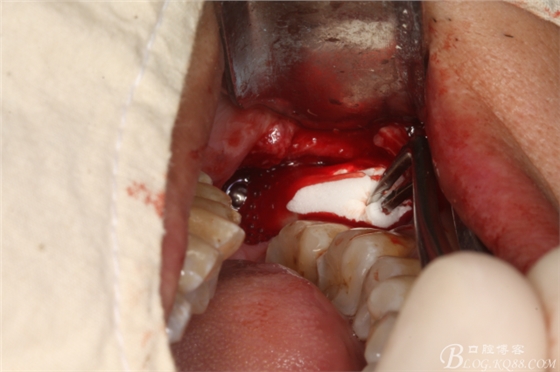

圖10.創(chuàng)口內(nèi)放置膠原蛋白海綿